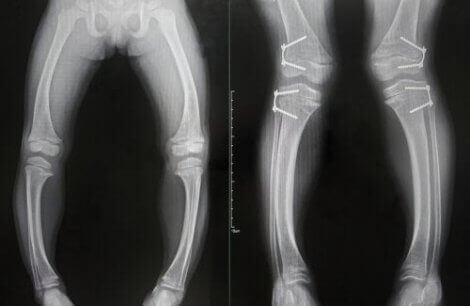

- Deformasjoner i benvevet, som mykner. Denne tilstanden vil sannsynligvis forårsake bøyde ben hos de som lider av den. Det kan også føre til slitasje i endene av noen bein.

Diagnostiseringen av denne tilstanden er basert på kombinasjonen av endrede analytiske og radiografiske funn og tilstedeværelsen av de typiske kliniske symptomene vi forklarte ovenfor.